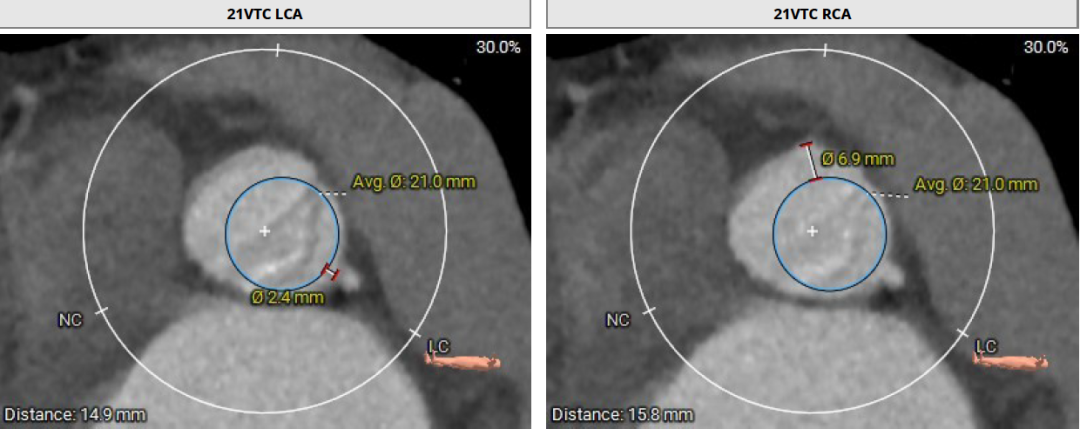

患者Type1 二叶瓣,右无融合,融合嵴钙化,钙化主要分布瓣叶缘和融合嵴处,无冠窦底钙化向下延伸至流出道4mm处。Annulus面积398mm²,LVOT面积400mm²,SOV 27.6-30.9mm,STJ高度21.3mm,内径29-32.7mm,瓣环角度62°,升主动脉扩张,左冠高度14.9mm,左冠瓣叶长度15.7mm,右冠高度15.8mm,右冠瓣叶长度9.2mm,模拟植入21#瓣膜VTC LCA 2.4mm,右侧髂内分叉处可见钙化,右侧髂外动脉最细为6.1mm,左侧髂外动脉最细为6.1mm,外周入路尚可。

瓣环:Annulus Dimensions - Area:398.2 mm² ;左室流出道(瓣下3mm)Area:400.5 mm²

使用Supra annulus画圆法评估21# RENATUS瓣膜植入情况: